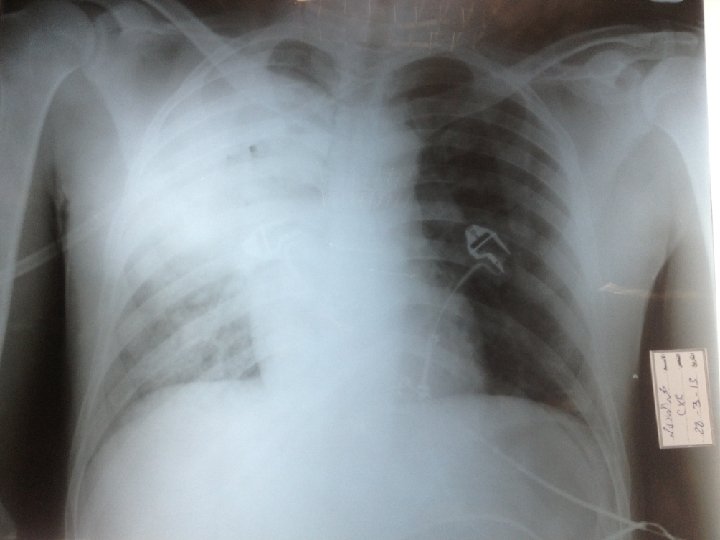

Pt was admitted to room A at 2: 00 pm 29 yrs old male whose known to be DM for 7 yrs on mixtard insuline presented with cough , SOB, and fever for 7 days prior to the presentation for which he received amoxicillin clavunate tabs without any significant improvement. OE: pt looks ill tachypnic vitals signs : - Pulse 144 - Bp 16080 - SPO 2 65% on room air - RBS 257 - Chest : bronchial breathing , and decrease air entery on the RT side.

SO , the pt was diagnose as pneumonia At 9: 30 pm pt was admitted to CCR. On admission he was looking ill , tachypnic on NRM. A : his airway was patent, on NRM B : RR 39, SPO 2 85, both sides of the chest moving equally, there was bronchial breathing and decrease breath sounds on Rt side. C : pulse 130, BP 11980 D : GCS 1515 , RBS 296 E : examination of all other systems were unremarkable.